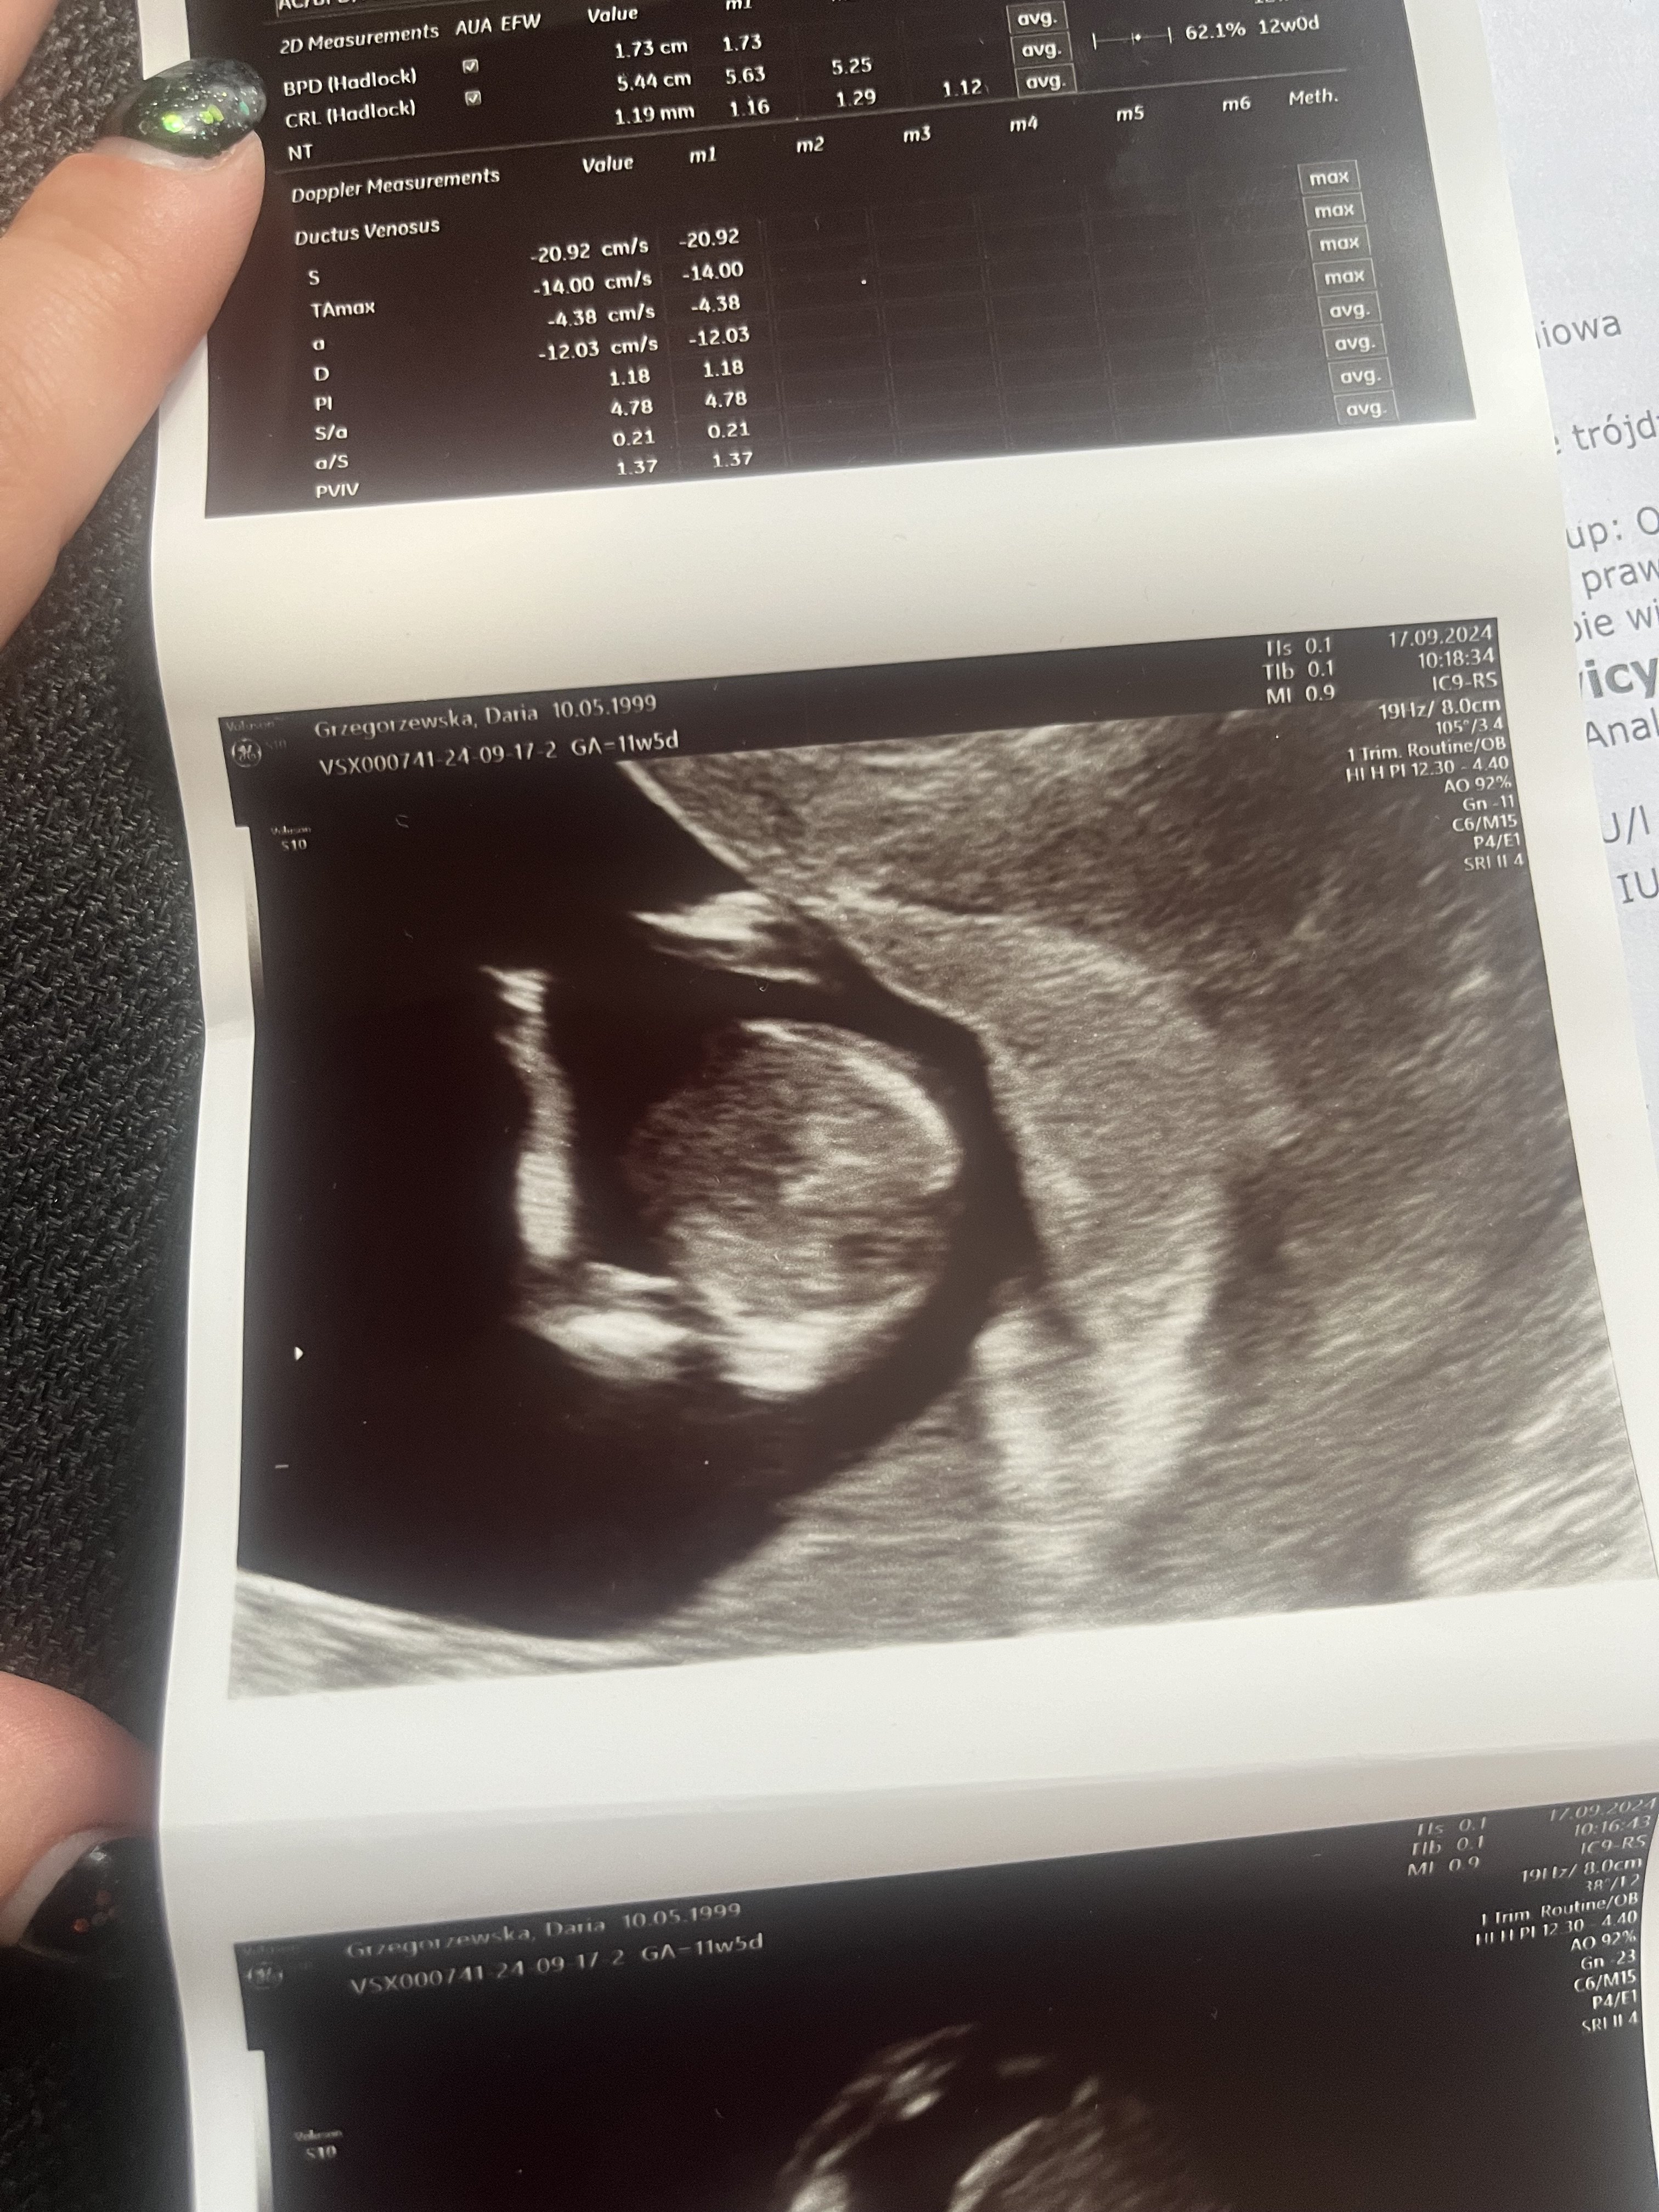

Cześć jestem w 18 tc ciąży i trafiła mi się dziwna sytuacja w 12 tc ciąży Pani na prenatalnych stwierdziła, że ona widzi dziewczynkę, parę dni później byłam u ginekologa przedłużyć L4 bo mi się kończyło i lekarz spojrzał i powiedział,że chłopiec trochę przyznam się zszokowałam bo nie było różnicy jakiejś dużej pomiędzy tymi usg a u tego Pana usg trwało może z 2 minuty, a ta Pani z prenatalnego była miałam wrażenie bardziej dokładna.Dodam jeszcze,że na tej wizycie u tego Pana dziecko było źle obrócone pleckami i lekarz stwierdził że coś tam dynda ale był taki pewny siebie,że to chłopiec i mnie to wkurzało bo uważam,że nigdy nie powinno mieć się 100% pewności. Sama obróciłam do siebie wtedy ekran bo on sam z siebie nie chciał mi go pokazać,co mnie również zirytowało bo jak można nie pokazać matce usg własnego dziecka. Dlatego ostatnie zdjęcia które mam to właśnie z 12 tc, bo ten Pan mi nie raczył dać takiego zdjęcia żebym miała na pamiątkę czy do porównania, stąd moja niepewność i coś temu Panu nie ufam.Bardzo marzy mi się dziewczynka i mam nadzieję,że to jednak faktycznie będzie dziewczynka. Niżej wrzucam zdjęcie z tego 12 tc.

IMG_2420.jpeg

No niby tak szkoda ,że mi tamten typ nie dał zdjęcia bo tak to muszę do połówkowego czekać mam za parę dni,stresuje się trochę. Pani na pierwszych prenatalnych mówiła że tak dziewczynka na 80%. Mam nadzieję, że mi to potwierdzi za parę dni.

Ale na tym zdjęciu nic bys nie znalazła. Po prostu za wcześnie.

Pani z pierwszych prenatalnych też troche strzałem. Ja bym nie patrzyla ani na to ani na to. Poczekaj, zaraz masz połówkowe.